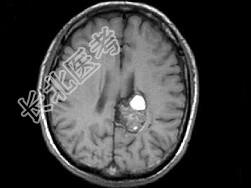

- 单项选择题男,59岁, 反复头晕头痛半年余,重体力活时头痛明显, 根据所提供图像,最可能的诊断是 ( )

A、(左顶)海绵状血管瘤

B、(左顶)室管膜瘤

C、(左侧脑室)胶质瘤

D、(左侧脑室)脉络膜乳头状瘤

E、(左顶)动静脉血管畸形